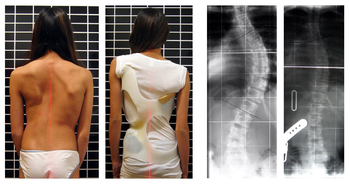

Scoliosis is a medical condition that refers to the abnormal curvature of the spine typically curving into a ‘C’-shape or ‘S’-shape when look at from the back (which becomes exceptionally clearer with spine X-ray).